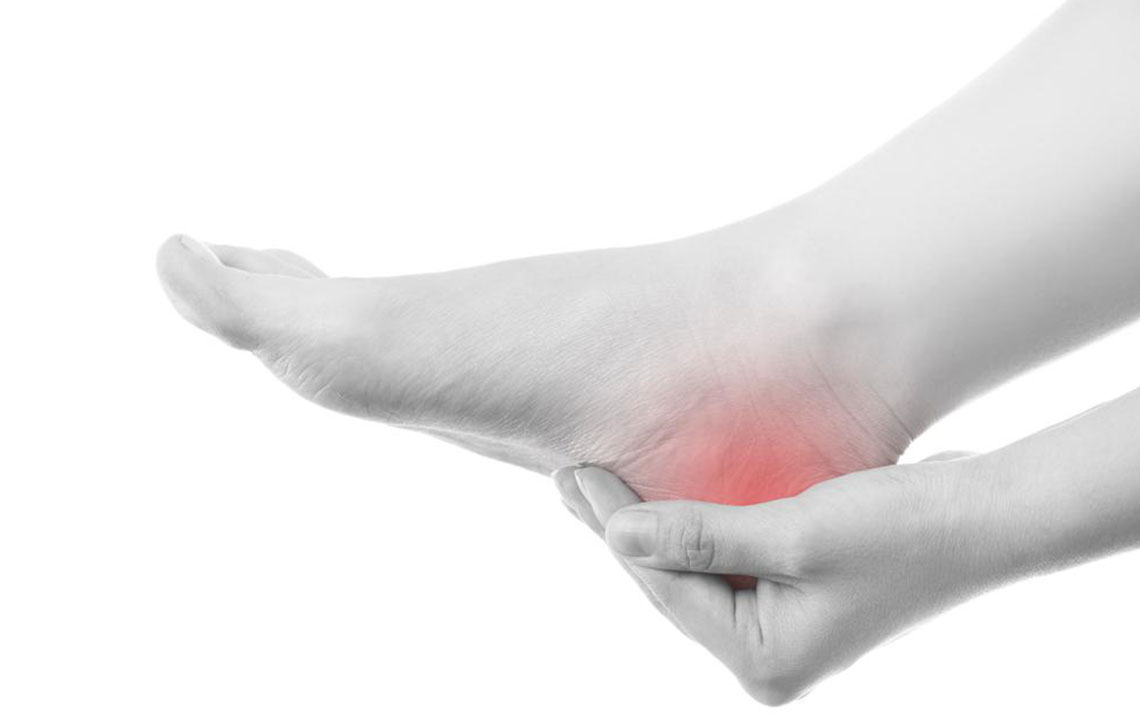

A gout is a form of arthritis, which develops due to the high level of uric acid in the blood. The acid creates a sensation which feels like needle-like crystals in the joints, which cause sudden, episodic pain, redness, swelling, tenderness, etc. Before knowing the popular and effective ways of treating gout pain, let’s understand the four types of gout pain that include asymptomatic hyperuricemia, acute gout, interval gout, and chronic gout.